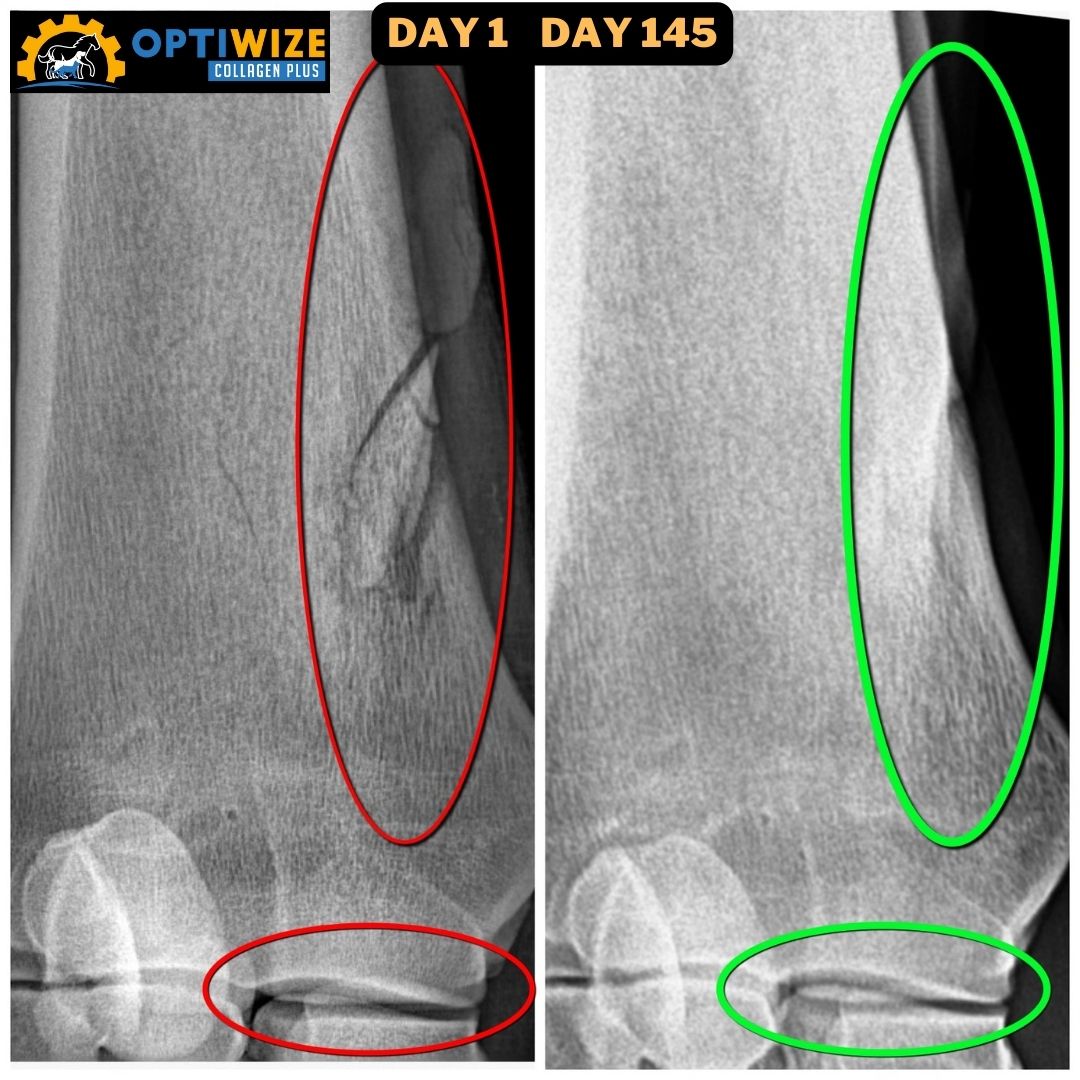

• X-ray, fracture Day 1 vs. Day 145.